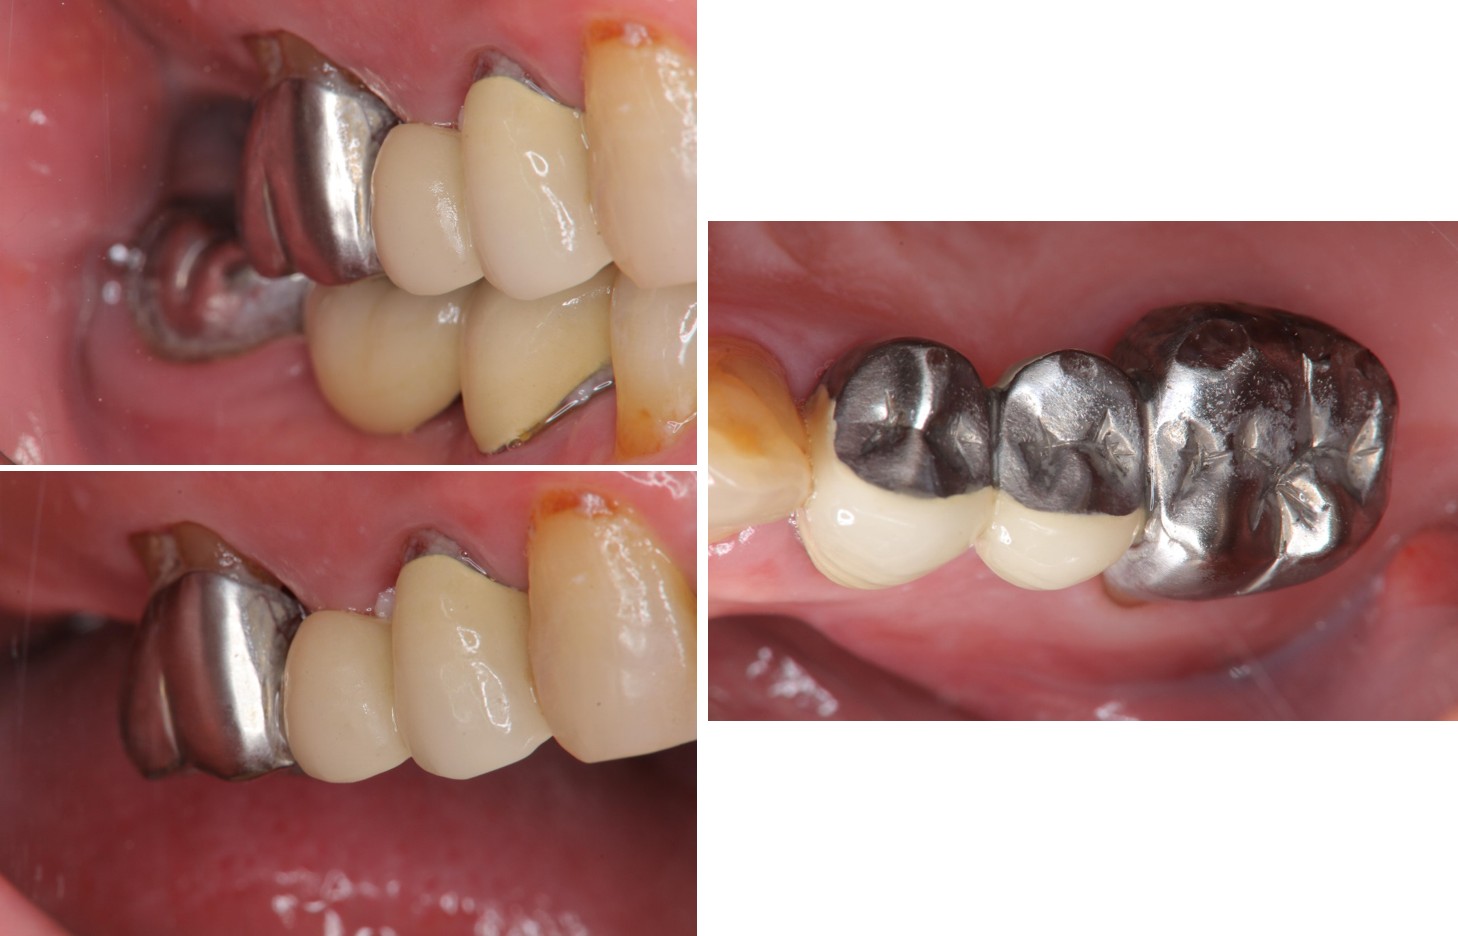

膺復前評估牙齦、牙齒狀態

治療後,牙周咬合良好

治療後,密合度良好

術前、術後比較